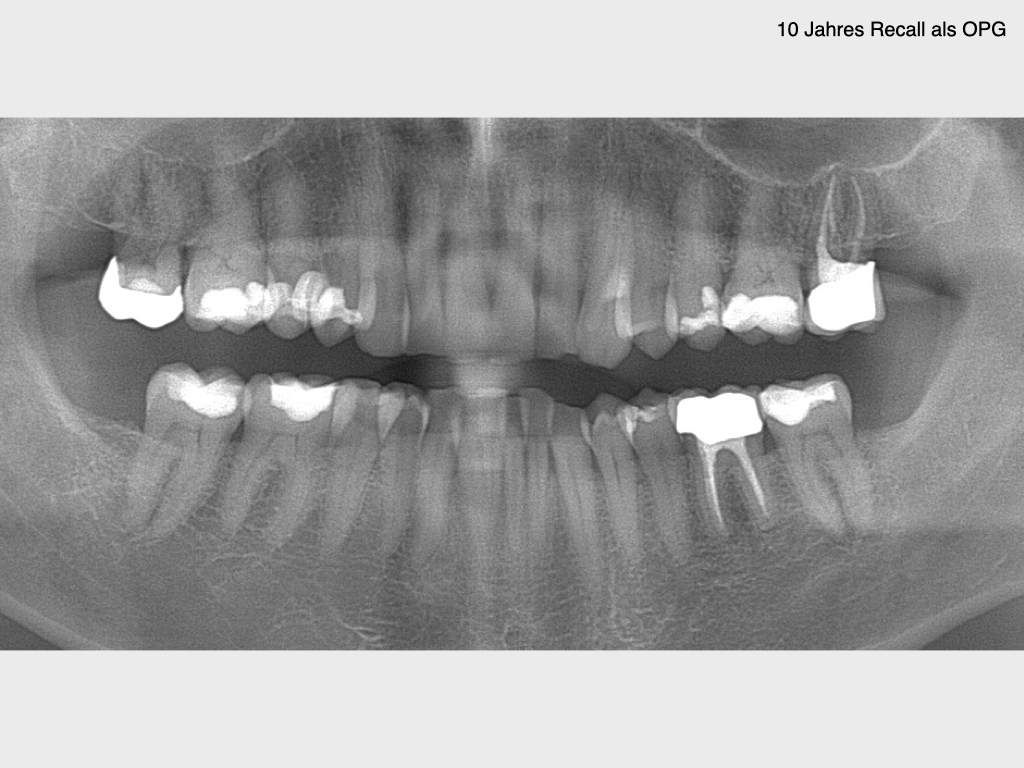

10 Jahres Recall